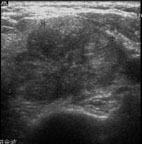

蔡先生因在左頸有腫塊而到耳鼻喉科門診就診(圖5),頭頸部的局部檢查除了左頸有界限糢糊不清的腫塊外其它包括鼻咽部(圖6)並沒有明顯異常,以頭頸部超音波檢查發現淋巴結預測值高於7分(圖7),超音波導引下細針穿刺細胞學檢查懷疑是轉移性鼻咽癌後,接受內視鏡鼻咽部切片證實為鼻咽癌。由於蔡先生超音波導引下細針穿刺細胞學檢查,避免了過去常見的頸部腫塊的切片手術。蔡先生接受放射腺治療後,腫塊即消失,因此可見頸部腫塊的切片手術對於鼻咽癌的診斷治療是不必要的。

圖5. 蔡先生因在左頸有界限糢糊不清的腫塊而到耳鼻喉科就診

圖7. 頭頸部軟組織超音波檢查,惡性淋巴結預測值高於7分,超音波導引下細針穿刺懷疑是轉移性鼻咽癌,後由鼻咽部切片證實為鼻咽癌